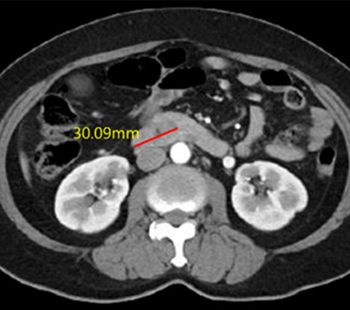

2025.3.14 腹部CT

肝内胆管癌 4期

60日集中 高频热疗 实施